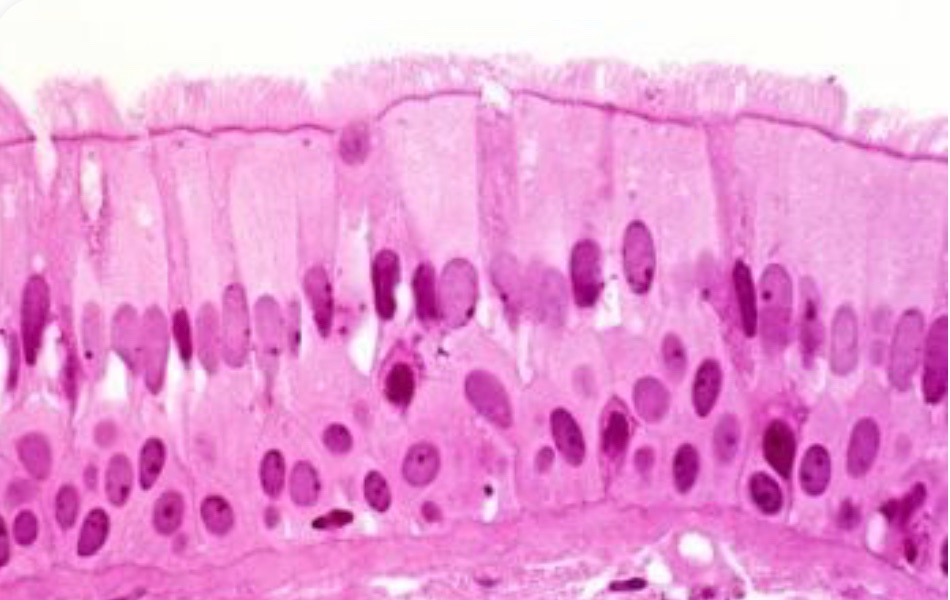

1 Tissue ประเภทใด

2 เป็นเซลล์ชนิดใด

5 จากภาพเป็นเนื้อเยื่อชนิดใด

8 จากภาพเป็นเซลล์ใด

9 A and B คือเซลล์อะไร ตามลำดับ

10 จากภาพคือเซลล์ใด